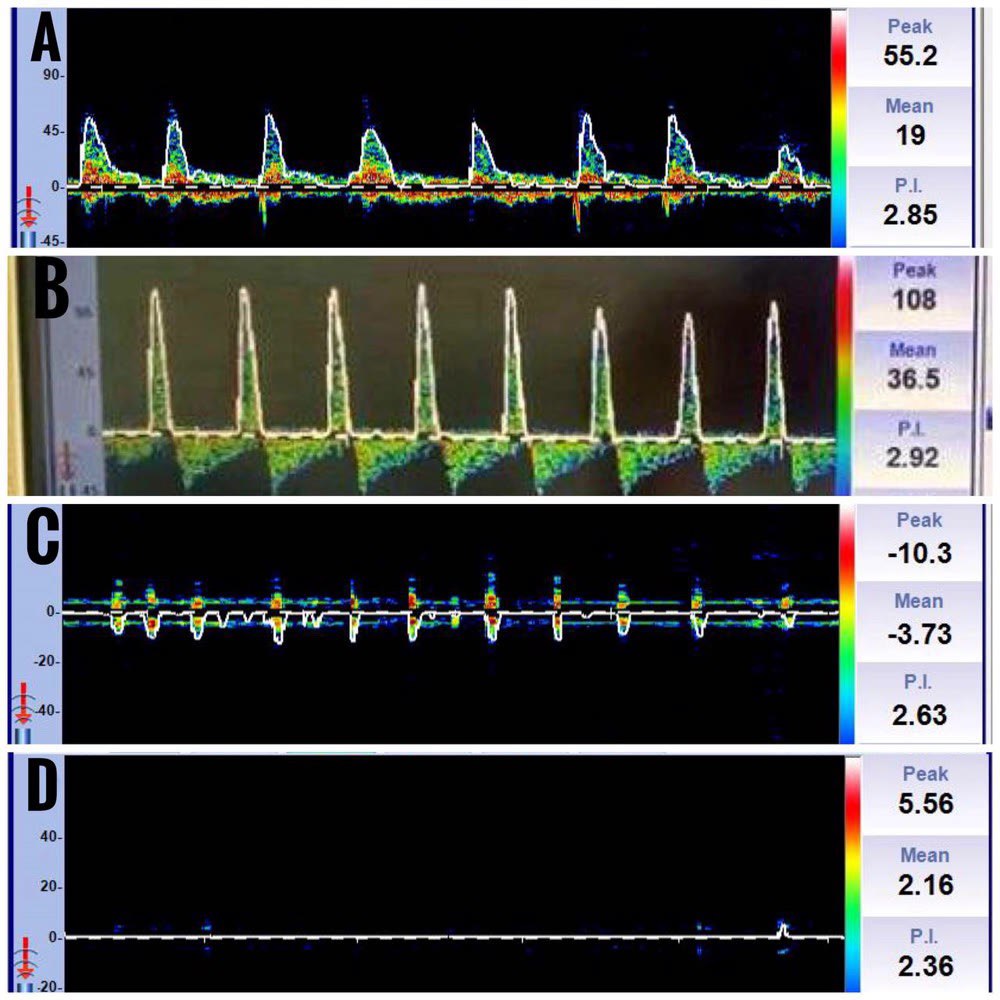

An increase in ICP causes elevated cerebrovascular resistance in the distal blood vessels. This manifests as an initial increase in PSV, a decrease in EDV, and an increase in the PI in the TCD. EDV reaches baseline when ICP equals diastolic pressure. In case of a further increase in the ICP equalling systolic pressure, oscillating flow is observed, wherein forward and reverse flow components in one cardiac cycle exhibit almost the same area. Systolic spikes are seen when ICP is more than systolic pressure, which is highly suggestive of cerebral circulatory arrest when present bilaterally. They are sharp unidirectional velocity signals in early systole of less than 200 ms duration, less than 50 cm/sec, and without a flow signal during the remaining cardiac cycle. Gradually, systolic spikes will disappear, and no flow signals can be observed (Figure 16).

(A) Decrease in mean flow velocity and end-diastolic velocity, (B) Diastolic flow reversal, (C) Waveforms resembling systolic spikes, (D) No flow state